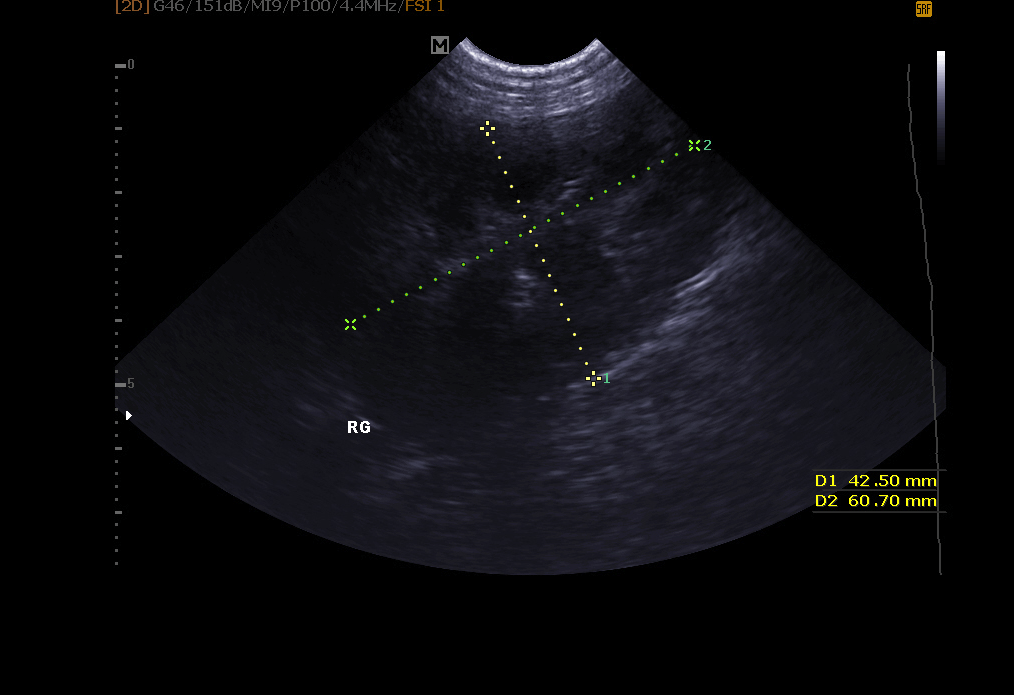

Echographie abdominale: elle permet l’exploration de le vessie (recherche de calculs, polypes, tumeur), des reins, de la rate , du foie , du pancréas et autres organes abdominaux.